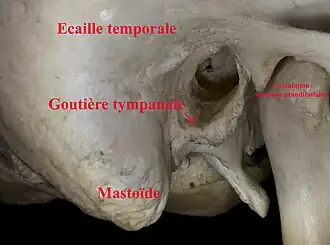

- la partie osseuse est creusée dans l'os temporal et représente la moitié du conduit, soit 14 à 16 mm. Elle est constituée de la gouttière tympanale, qui est soudée à l'écaille temporale.

Conduit auditif externe droit (Ostéologie)